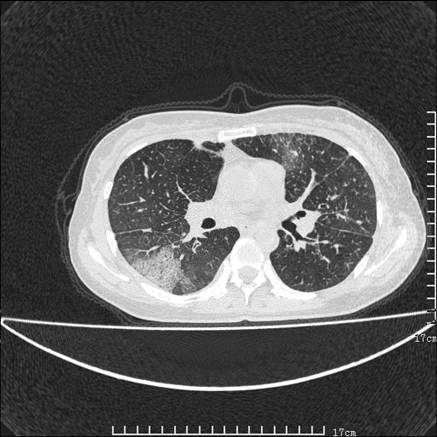

女,46岁,患胃溃疡多年,溃疡大小约1.0cm左右,后于5年前手术,病理为胃癌。主诉:半月前感冒后胸闷,气短,有咳嗽,无明显咳痰,无发热。偶有腰背部不适。

以下为高分辨扫描图像

双肺小叶间增厚,双肺散布粟米影和磨玻璃状影,以双肺上叶为重。结合病史考虑转移(癌性淋巴细管炎)可能性大。

结合病史:认为是典型肺部癌性淋巴管炎、淋巴结转移。请看图解。

正如caihe主任所言,影像表现结合临床病史应该支持肺癌性淋巴管炎;上肺大片边缘不清的渗出病变,多系感染所致,临床有感冒病史并咳嗽表现。肺癌性淋巴管炎临床一般无咳嗽、咳痰症状。

肺癌性淋巴管炎征象分为主要征象及合并征象,主要征象包括:

1、近肺门支气管血管周围间质结节状增厚;

2、小叶间隔结节状增厚;

3、小叶中央间质结节状增厚;

4、胸膜下间质结节状增厚。

合并征象为:纵隔淋巴结增大,胸腔积液,肺多发随机分布的小结节等。